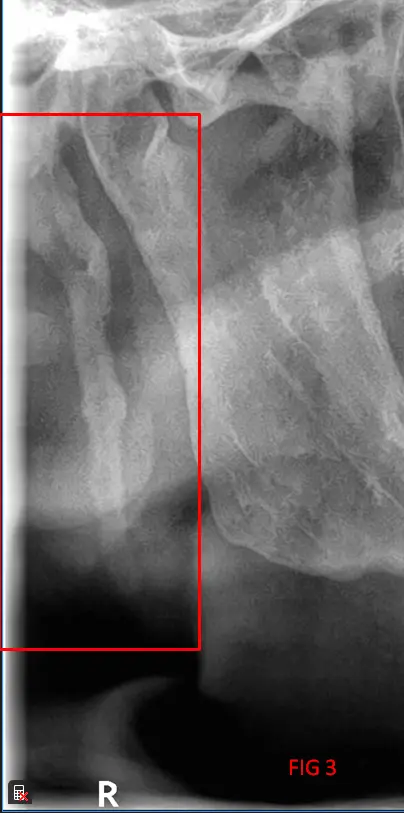

​En el análisis de la ortopantomografía, se identifican estructuras radiopacas bilaterales de morfología alargada. Estas formaciones se extienden desde la base del cráneo (apófisis estiloides) con una trayectoria descendente y anterior hacia el hueso hioides (FIG 1, 2 y 3). Basándose en las características imagenológicas, se concluye que se trata de una osificación bilateral del ligamento estilohioideo, un hallazgo que suele presentarse de forma incidental